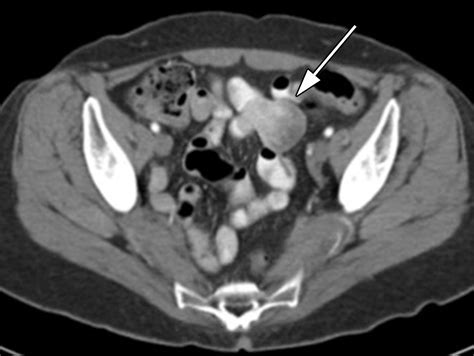

CT or MRI Enterography Cross-sectional imaging that cater detailed views of the enteric paries and smother construction.